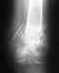

В 2004 году перелом правой лучевой кости осколок со смещением,сделали пластину наверх 4 винта,один загноился,через 3 месяца,удалили пластину.Через 6 месяцев случился перелом,кость скривилась от кисти к соседней кости,в гипсе 2 месяца.Еще через 4 месяца сделали операцию "секвестртомию",через 1.5 месяца аппарат Илизарова, выровняли кость, потом 3 месяца фиксации, дали группу 2007-2008год.Сейчас снимок томографии.